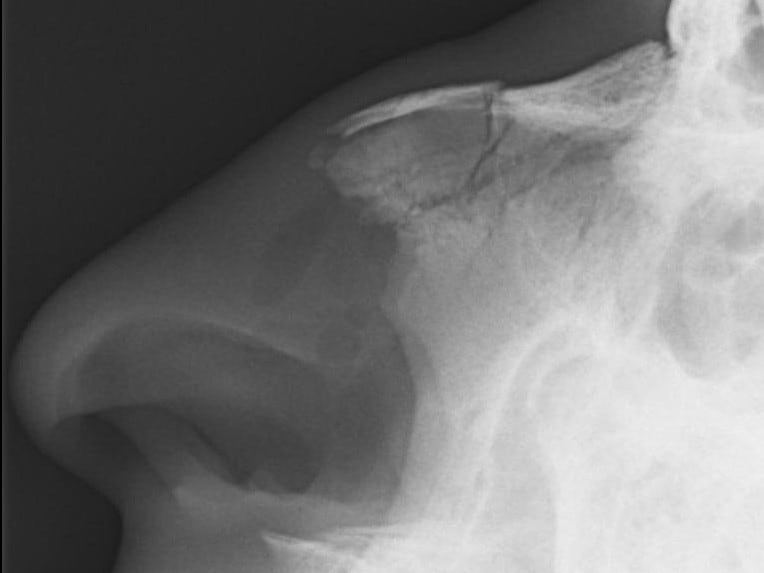

इसके बाद डॉक्टर आपके नाक की जांच करता है जिसमें नाक का शेप, हड्डियों की स्थिति, क्षतिग्रस्त हिस्से की कोमलता और विकृति, नाक के परदे की जांच की जाती है। लाइट और एक उपकरण की मदद से डॉक्टर आपकी नाक के अंदरुनी हिस्से की जांच करता है कि कहीं कोई ब्लड क्लॉट, नील आदि तो नहीं है। अधिकांश मामलों में निदान के लिए और किसी टेस्ट की जरूरत नहीं पड़ती है। एक्स-रे करना हमेशा आवश्यक नहीं होता है।